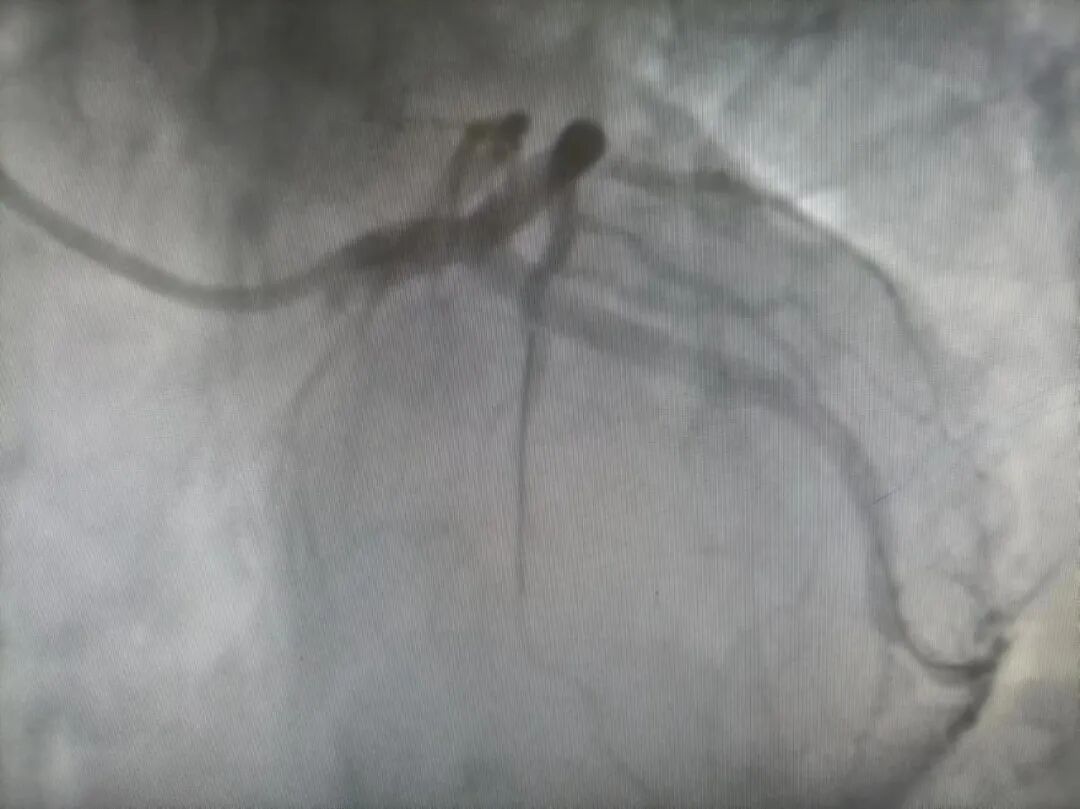

一个病例分享:一位37岁男性病人胸痛胸闷1小时50分入院,自诉无明显诱因出现胸痛胸闷症状,位于心前区、胸骨中段,持续性疼痛,伴大汗、恶心,测血压82/50mmHg,急查心电图示异位心律,广泛前壁心肌梗死,患者病情危重,立即推入导管室行冠脉造影术,冠脉造影显示左主干末端负荷血栓,前降支开口100%闭塞,回旋支开口90%狭窄,可见血栓影,给予血栓抽吸,抽吸出大量红色血栓,后于前降支开口植入支架一枚,七天后患者好转出院,这样的例子数不胜数,无数次的在时间与生命赛道上与死神抢病人。

造影前